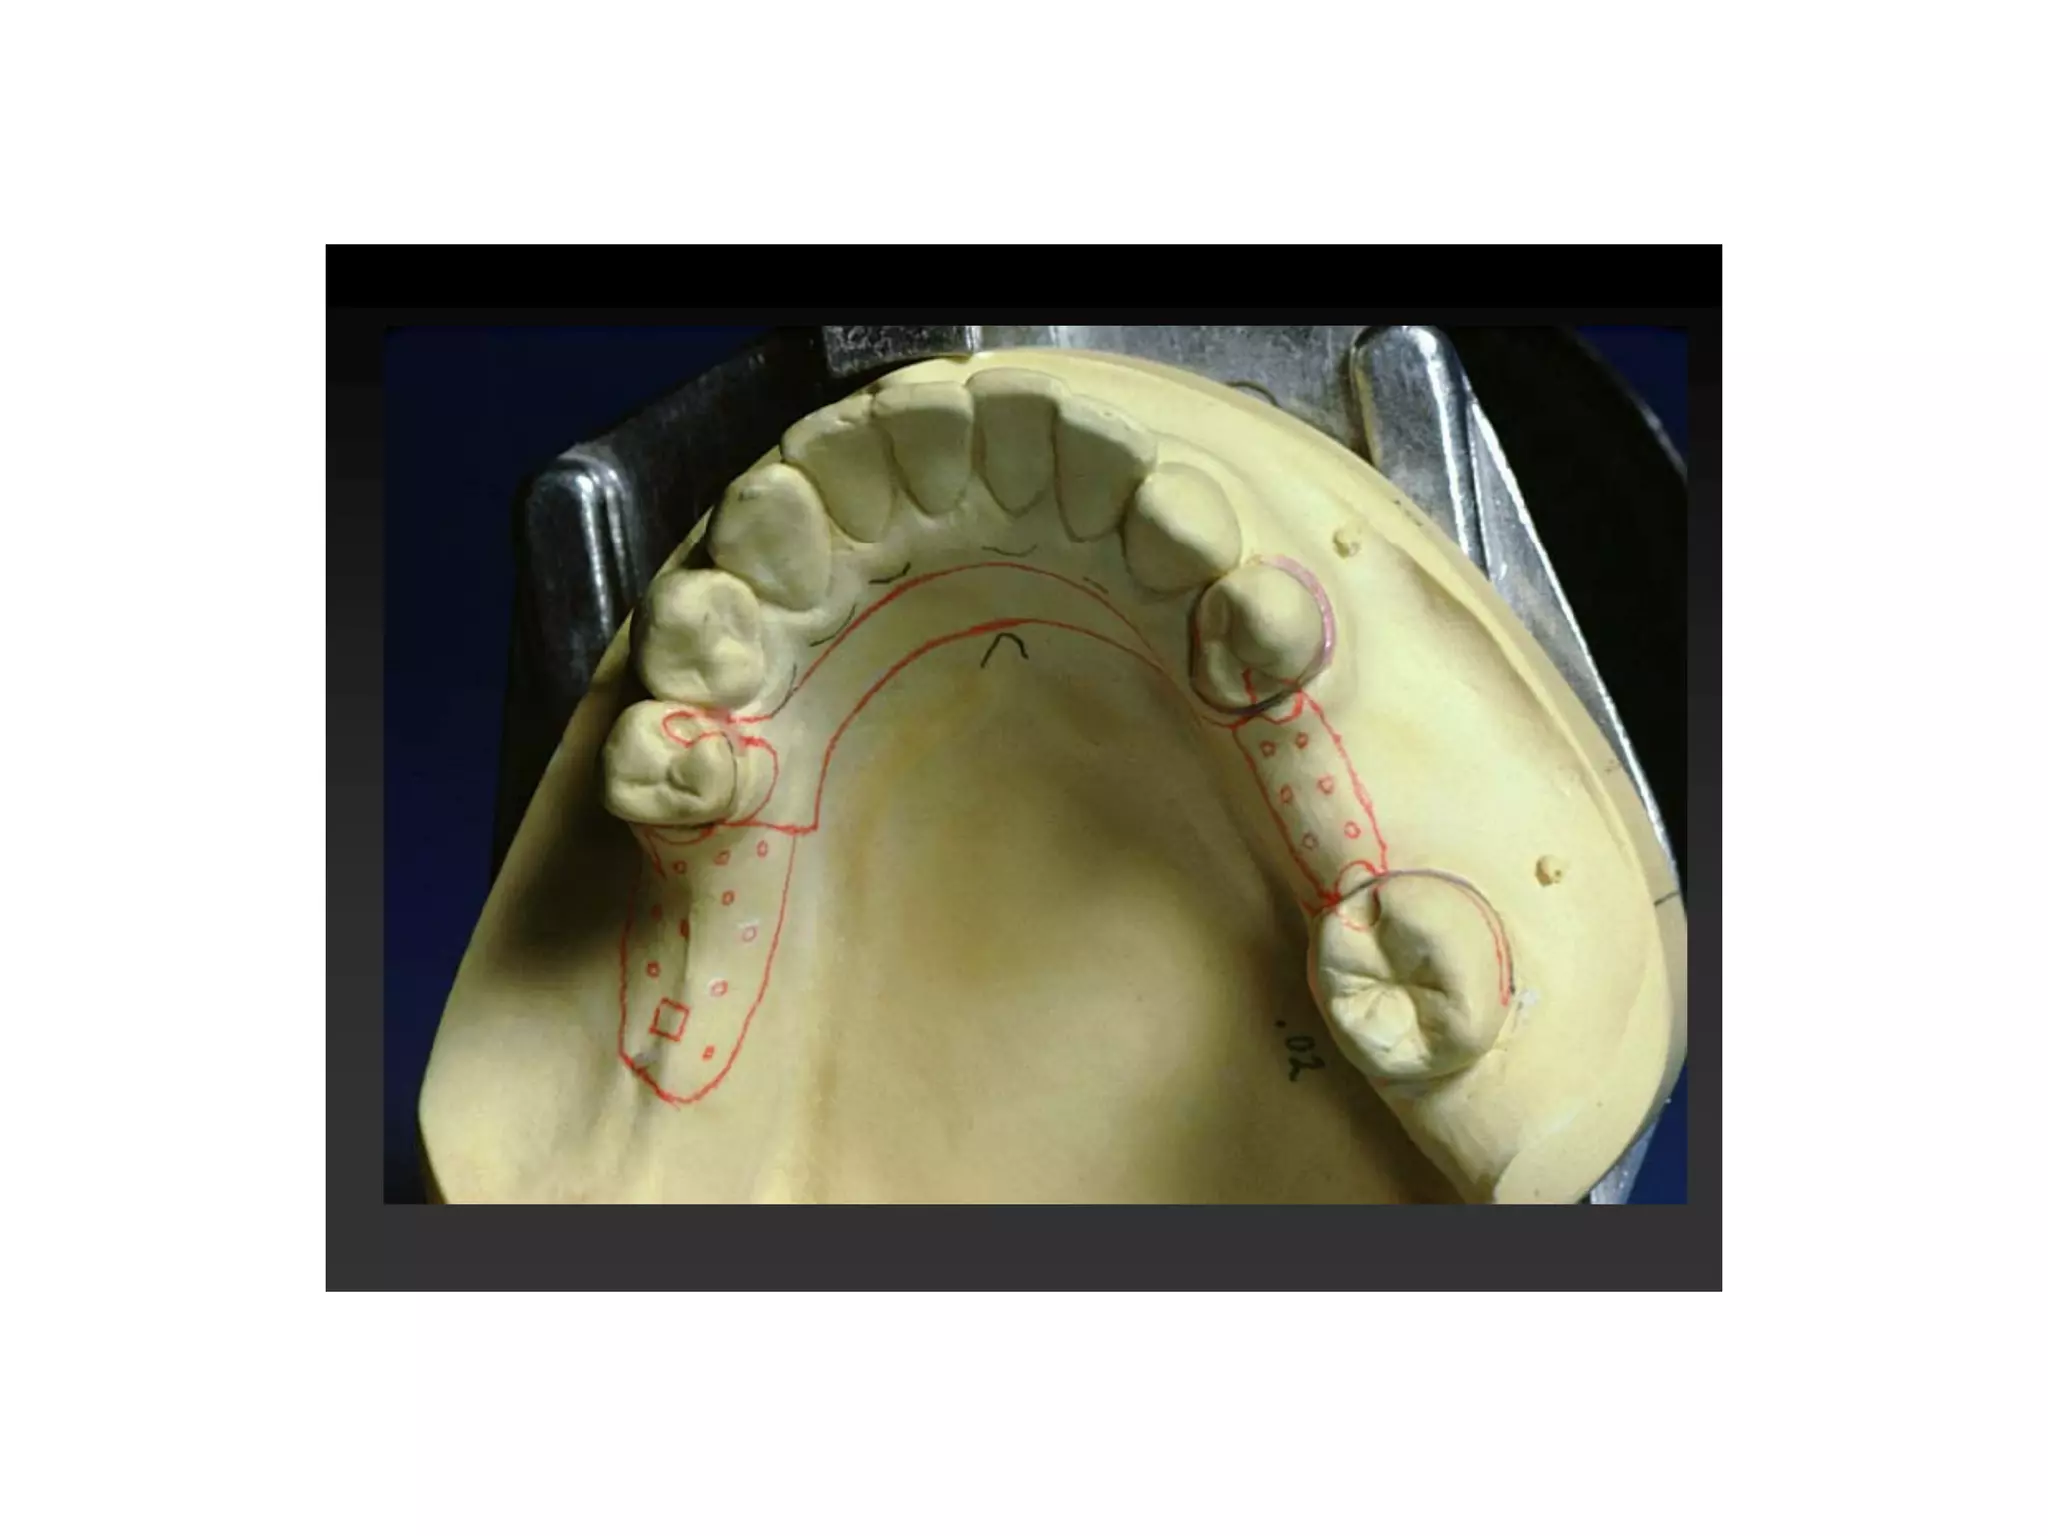

O : Outline the saddle areas :

A decision must be made on which missing teeth require replacement and

saddle areas marked accordingly on an occlusal view of the dental arch

consequently :

•The kennedy classification of the case.

•The primary abutment teeth are determined.

•The number of guiding planes are determined.

•The most appropriate AP tilt is determined.

Class I Kennedy

Primary abutments : 20 and 29

Potential guiding planes

Posterior saddle : Anterior tilt !

GP 1 GP 2